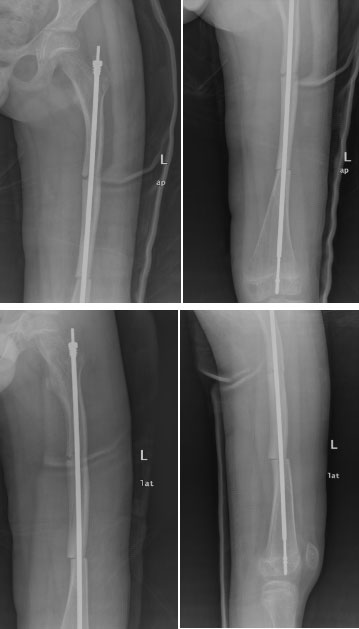

面對(duì)成骨不全的特殊病例,小兒骨科采用目前最先進(jìn)、最可靠的手術(shù)方式,選擇左股骨骨折切開復(fù)位、左股骨弓形變截骨矯形可延長(zhǎng)髓內(nèi)釘內(nèi)固定術(shù)。在小兒骨科及麻醉科的共同配合下,手術(shù)歷經(jīng)2.5小時(shí),圓滿順利完成。

圖為患者股骨弓形變截骨矯形可延長(zhǎng)釘內(nèi)固定術(shù)后影像學(xué)資料

術(shù)后小兒骨科按照術(shù)前制定的護(hù)理及康復(fù)方案,從術(shù)后傷口護(hù)理、體位護(hù)理、下床訓(xùn)練、扶拐行走訓(xùn)練等各方面指導(dǎo)患者進(jìn)行康復(fù)?;颊哂诮谥斡鲈?。這是玉溪市中醫(yī)醫(yī)院獨(dú)立完成的首例兒童成骨不全截骨矯形骨延長(zhǎng)手術(shù),標(biāo)志著我院治療成骨不全邁上了一個(gè)新臺(tái)階。